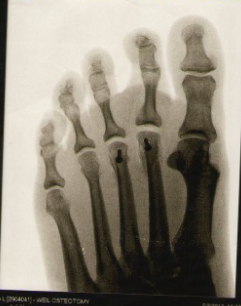

무지외반증은 모양만으로는 진단할 수 없고, 꼭 전문의와의 상담과 엑스레이 검사가 필요합니다. 엑스레이 검사를 하여 뼈사진을 보면서 엄지발가락의 각도와, 관절의 각도 등을 종합적으로 판단하여 전문의가 판단합니다.